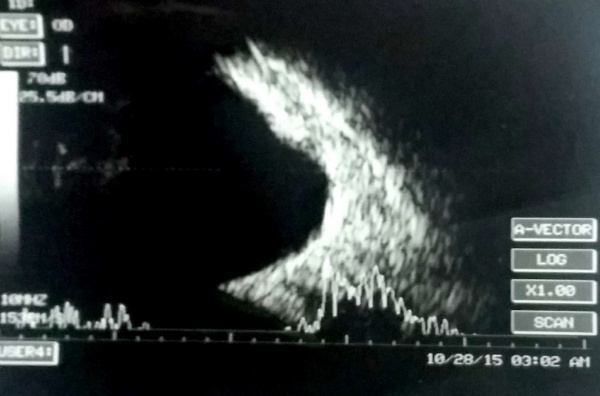

Note the after-movements of the PVD in this patient with subhyaloid hemorrhage and vitreous hemorrhage.